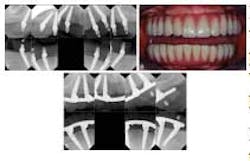

In the All-on-Four concept, four implants are used to support an acrylic, screw-retained provisional prosthesis, then a final prosthesis about four months later. Although this method uses only four implants, two of them are placed distally tilted in areas where bone height, nerve proximity, or other conditions make it impossible to place the implant axially. This tilting allows the placement of longer implants that have good anchorage in the best positions for prosthetic support. Previously, standard practice called for dental implants of at least 4.0 mm in diameter. For tilted implants in particular, this was considered the smallest diameter that could guarantee sufficient anchorage. The NobelActive implant, introduced in 2008, made it possible to use a 3.5 mm diameter implant for patients with atrophic jaws. Featuring tapering, a variable thread, and an inward tapered collar, this implant offers self-drilling capacity and bone compression qualities. High torque values can be reached, giving the implant high initial stability.RELATED |Fluoride treatment of synthetic biomaterial assists dental bone regeneration Prior studies have found that failed implants using the All-in-Four method were a result of soft bone and lower insertion torque values. The combination of a 3.5 mm diameter implant and the All-on-Four technique brings new treatment possibilities to patients with severe bone deficiencies.Full text of the article, “A New Approach to the All-on-Four Treatment Concept Using Narrow Platform NobelActive Implants,” Journal of Oral Implantology, Vol. 39, No.3, 2013, is available here.About Journal of Oral Implantology The Journal of Oral Implantology is the official publication of the American Academy of Implant Dentistry and of the American Academy of Implant Prosthodontics. It is dedicated to providing valuable information to general dentists, oral surgeons, prosthodontists, periodontists, scientists, clinicians, laboratory owners, and technicians, manufacturers, and educators. The JOI distinguishes itself as the first and oldest journal in the world devoted exclusively to implant dentistry. For more information about the journal or society, please visit their website.